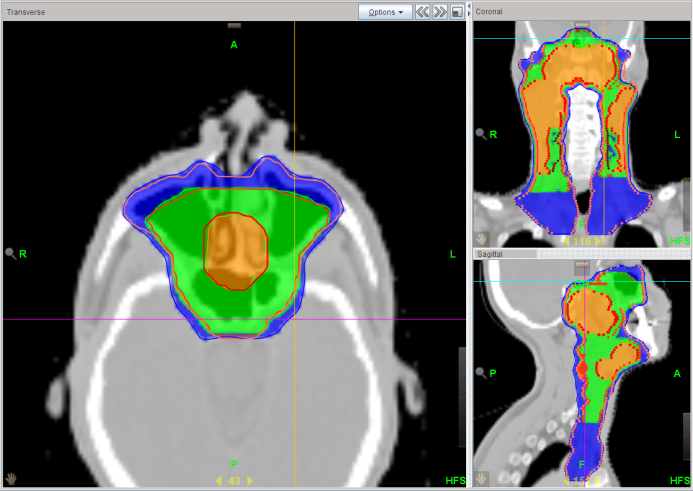

Chung Yin Mak

Score: 99.5/ 100

Hospital: St. Teresa’s Hospital

Technique: VMAT

Rank: 2017 Champion

Job Title: Radiation Therapist